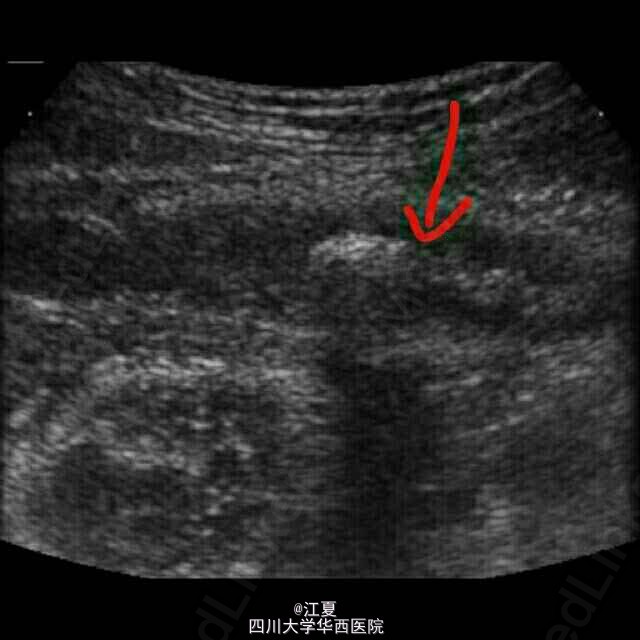

超声检查发现右下腹阑尾增厚伴积液,内含强回声团伴声影。

诊断: 急性阑尾炎伴阑尾结石。 治疗:手术切除阑尾。